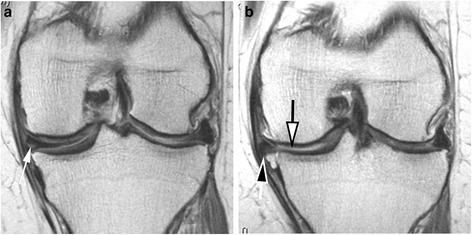

METHODS

We conducted a nested case-control study. Cases (n = 406) were knees having both radiographic and pain progression. Controls (n = 194) were knee osteoarthritis subjects who did not meet the case definition. Groups were matched for Kellgren-Lawrence grade and body mass index. MRIs were acquired using 3 T MRI systems and assessed using the semi-quantitative MOAKS system. MRIs were read at baseline and 24 months for cartilage damage, bone marrow lesions (BML), osteophytes, meniscal damage and extrusion, and Hoffa- and effusion-synovitis. We provide the definition and distribution of change in these biomarkers over time.

RESULTS

Seventy-three percent of the cases had subregions with BML worsening (vs. 66 % in controls) (p = 0.102). Little change in osteophytes was seen over 24 months. Twenty-eight percent of cases and 10 % of controls had worsening in meniscal scores in at least one subregion (p < 0.001). Seventy-three percent of cases and 53 % of controls had at least one area with worsening in cartilage surface area (p < 0.001). More cases experienced worsening in Hoffa- and effusion synovitis than controls (17 % vs. 6 % (p < 0.001); 41 % vs. 18 % (p < 0.001), respectively).

CONCLUSIONS

A wide range of MRI-detected structural pathologies was present in the FNIH cohort. More severe changes, especially for BMLs, cartilage and meniscal damage, were detected primarily among the case group suggesting that early changes in multiple structural domains are associated with radiographic worsening and symptomatic progression.